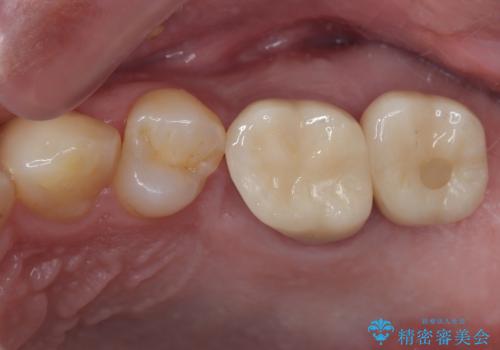

奥歯の大きなむし歯 神経を残してセラミック治療